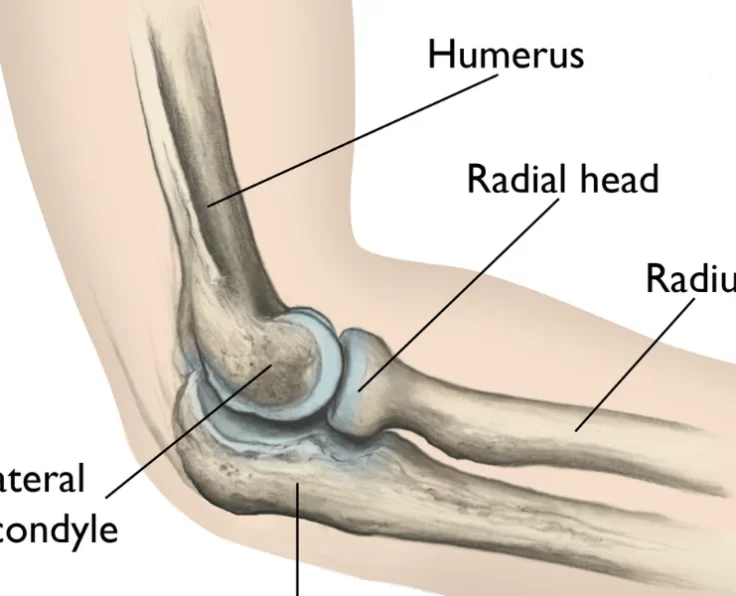

Elbow Arthroscopy

The term arthroscopy comes from Greek words that refer to the joint. In modern surgery, your surgeon uses a small camera and a video monitor…

Total Elbow Replacement

The elbow is an essential joint for regular everyday functioning, but it is susceptible to a variety of degenerative disorders as well as traumatic lesions…

Terrible Triad in Elbow

Three injuries are combined in a horrific triad: dislocation of the elbow, radial head fracture, and coronoid fracture.

Complex Fractures in Radial Head

They account for around a third of all elbow fractures and are most common in people between the ages of 20 and 60. (with a…

Capitellum Fractures

Capitellum fractures are a discrete subset of coronal plane partial articular injuries of the distal humerus, accounting for less than 1% of all elbow fractures.

Complex Distal Humeral Fracture

A distal humerus fracture occurs when the lower end of the upper arm bone (humerus) breaks, which is one of the three bones that make…